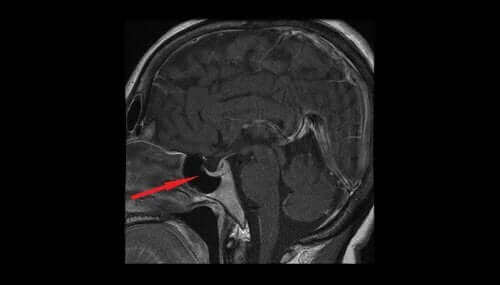

Хипофизната аденома: диагностика

Относно диагнозата, лекарят трябва да извърши физически преглед за да прецени дали има проблеми с двойното зрение и зрително поле. Също така, лаборантите проучват загубата на латералното или периферно зрение и способността да се гледа в определено области. Също така, те правят анализ на ендокринната функция за да видят признаци на излишък на хормони или други проблеми. Освен това, те могат да измерват параметри като повишени нива на кортозол, синдромът на Кушинг или твърде много от хормона на растежа.

Най-подходящите изследвания, които помагат за потвърждаване на диагнозата, са визуалното поле и компютърна томография и магнитен резонанс на мозъка.